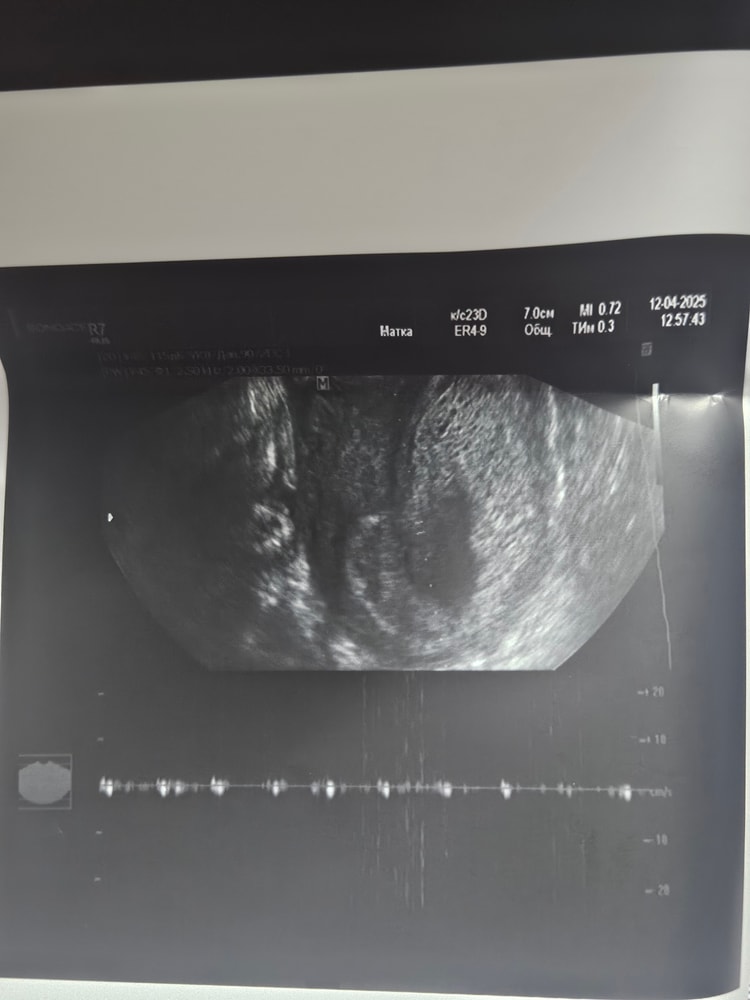

Беременность 9 недель. Сказали сделать контрольное УЗИ перед 1 скр. Сходила в платную клинику 11.04, эмбрион видно плохо( по словам УЗИ-специалиста рассасывается), СБ нет, поставили в заключении : "ЗБ 7.4 недель.Пузырный занос с множеством кист" . p.s: Ходила я на УЗИ 22.03 было СБ и эмбрион было видно. (За 2 недели-то меня что-то могло начать беспокоить).

12.04 я решила ещё в другую платную клинику сходить, эмбрион нашли с трудом(все так же не четко визуализируется), КТР 16мм, СБ +, прогрессирующая? ,тонус матки

прикреплю снимки узи за 12.04